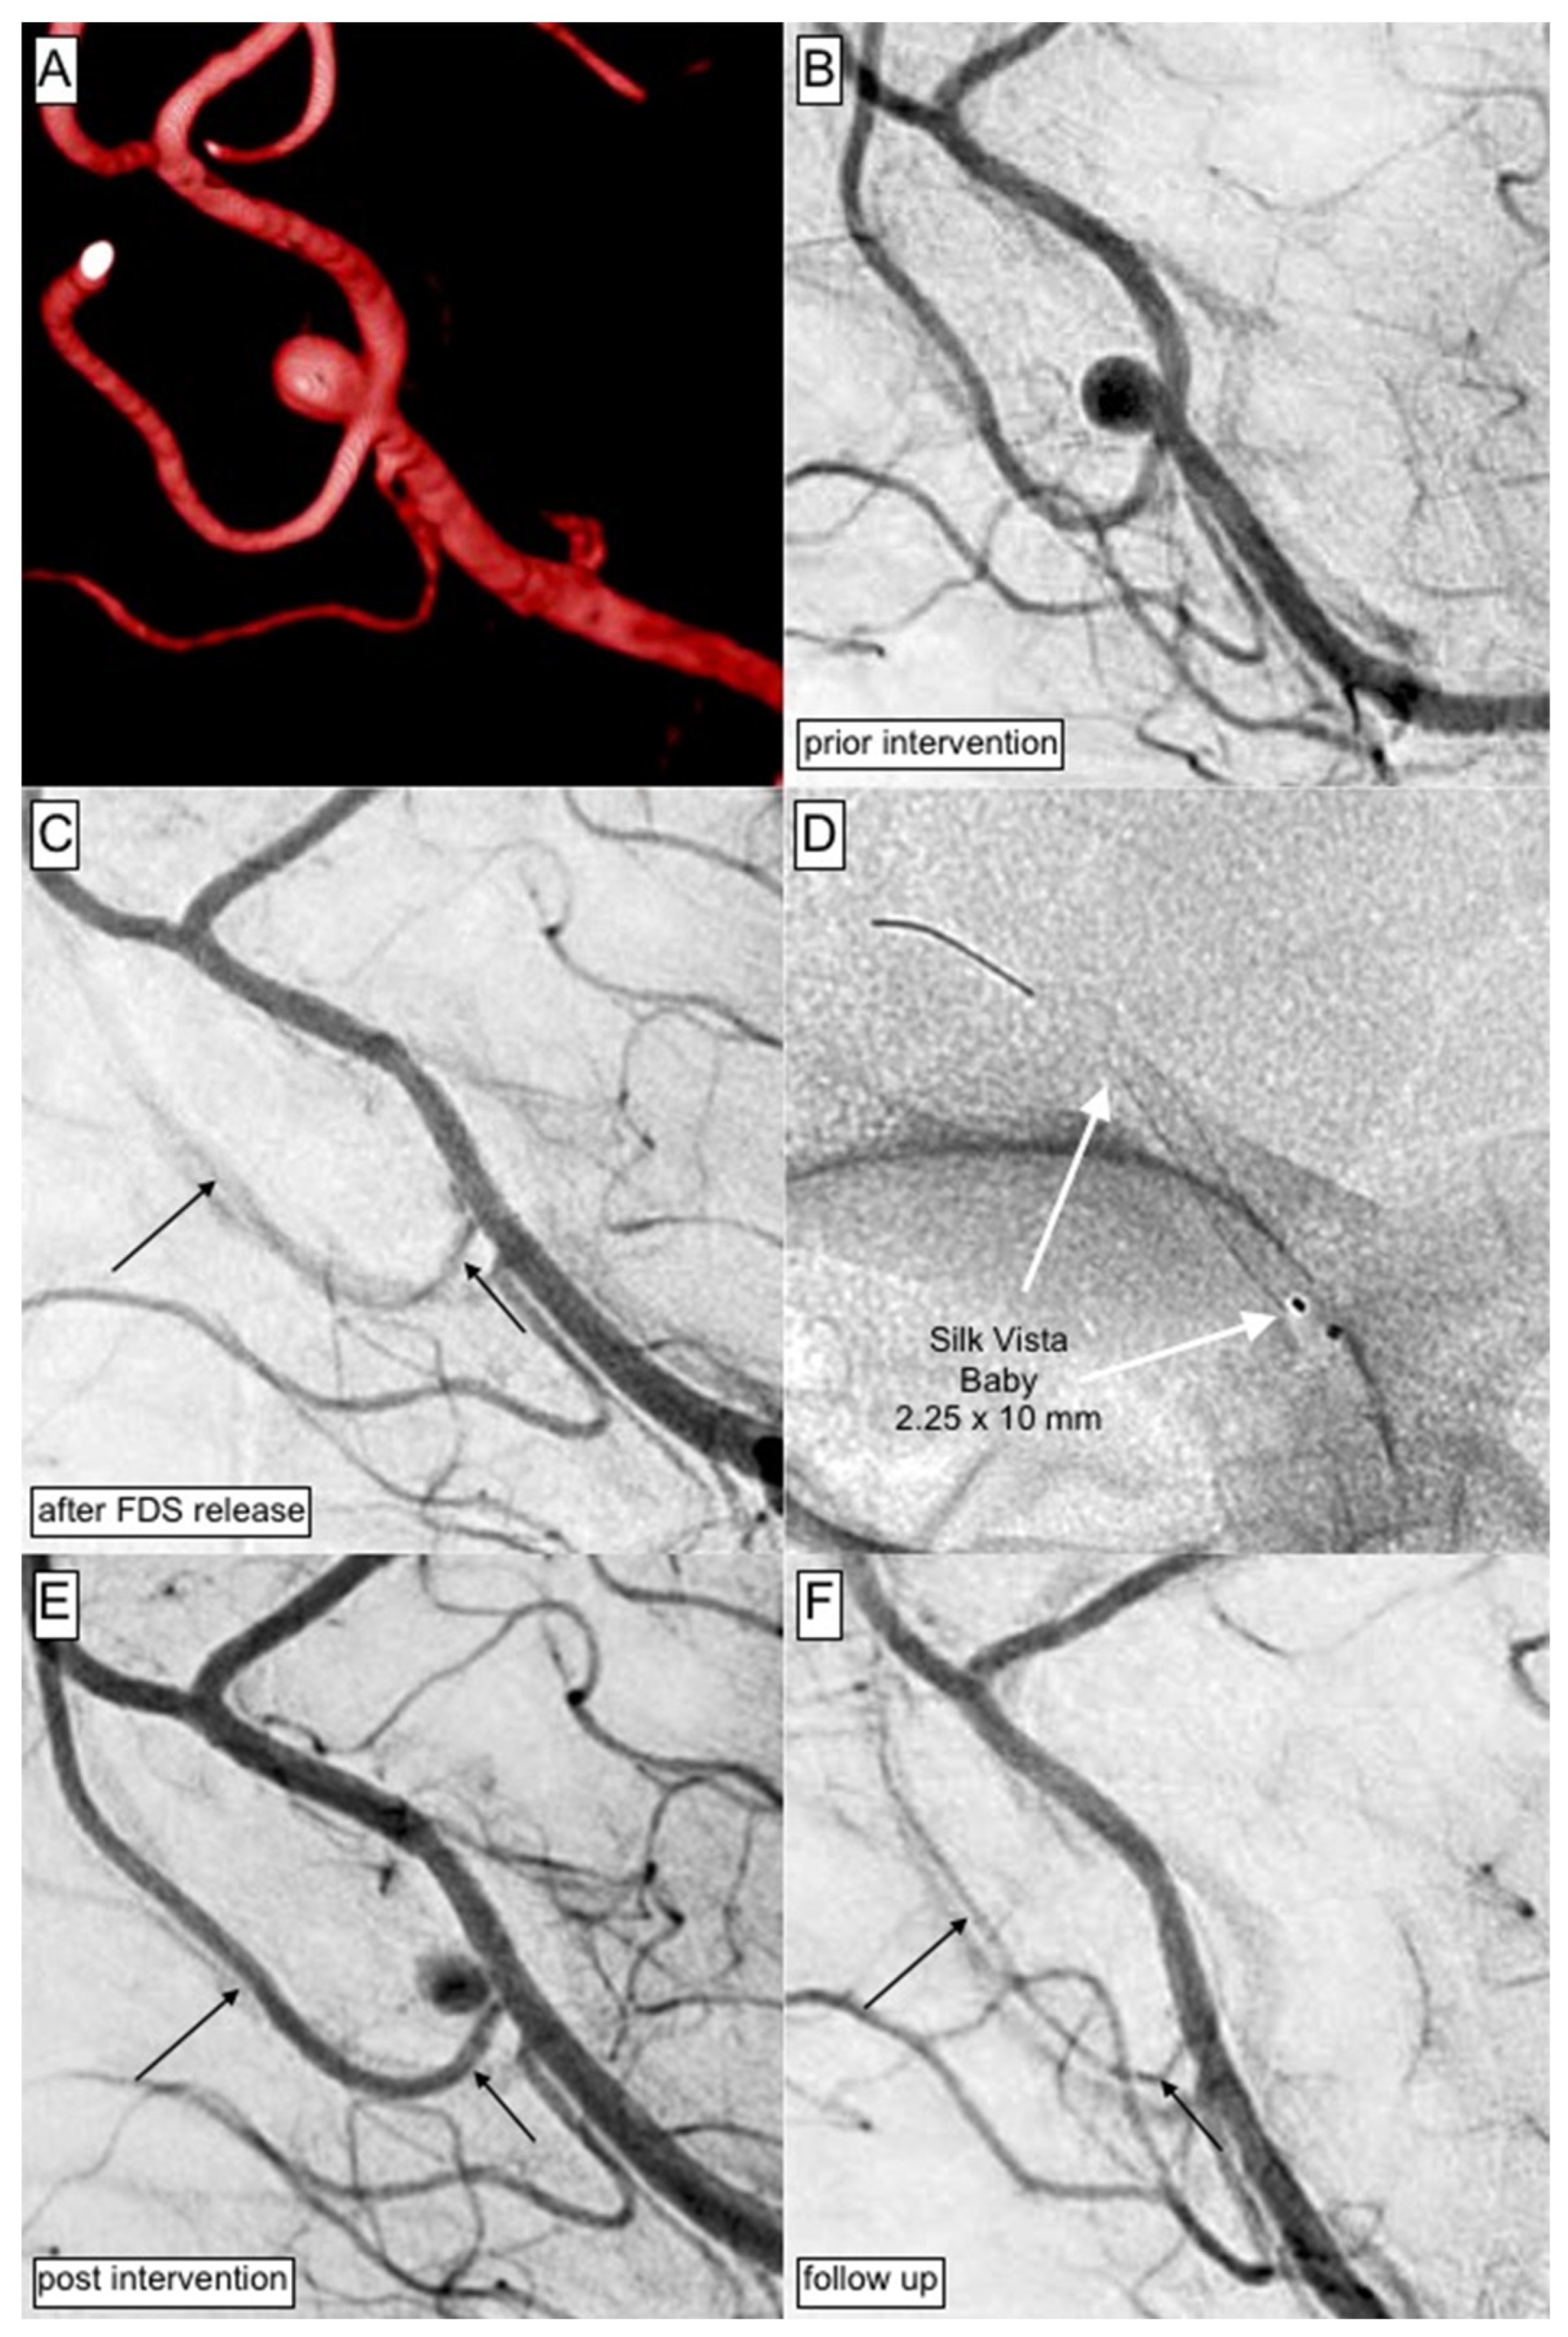

- Schüngel, M.-S.; Quäschling, U.; Weber, E.; Struck, M.F.; Maybaum, J.; Bailis, N.; Arlt, F.; Richter, C.; Hoffmann, K.-T.; Scherlach, C.; et al. Endovascular Treatment of Intracranial Aneurysms in Small Peripheral Vessel Segments-Efficacy and Intermediate Follow-Up Results of Flow Diversion With the Silk Vista Baby Low-Profile Flow Diverter. Front. Neurol. 2021, 12, 671915. [Google Scholar] [CrossRef]